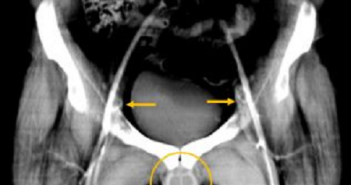

Em feito inédito, cirurgiões dos EUA testam com sucesso transplante de rim de porco em…